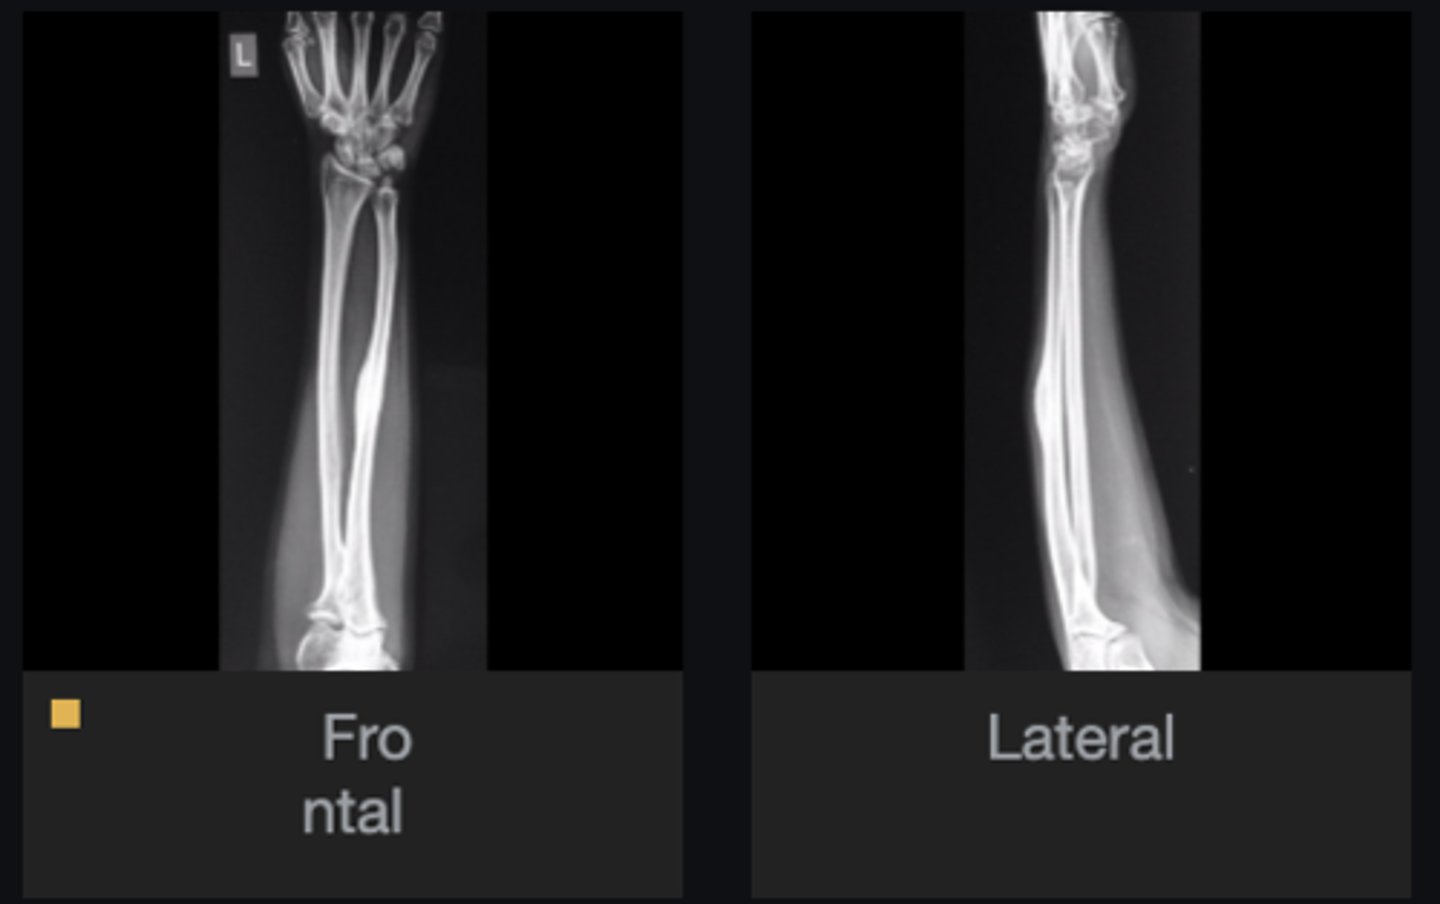

- Ulna

- Diaphysis

- Sclerotic

- Small, lucent nidus (< 1cm) in the cortex

- Geographic)

- Cortical thickening

Describe the lesion

<p>Describe the lesion</p>

Osteoid osteoma

Most likely diagnosis?

<p>Most likely diagnosis?</p>

29

New cards

Severe pain (worse at night, relieved by aspirin)

What is the hallmark history of a patient with this lesion?

<p>What is the hallmark history of a patient with this lesion?</p>

- Refer to orthopedist

- Adjust spine

Next step?

<p>Next step?</p>

None

Concerns/complications?

<p>Concerns/complications?</p>